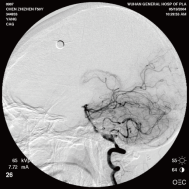

右侧颈内动脉后交通动脉瘤栓塞术前 左椎动脉造影 示左椎动脉夹层动脉瘤: 左椎动脉发出小脑后下动脉处呈囊性扩张,动脉瘤远端血管狭窄